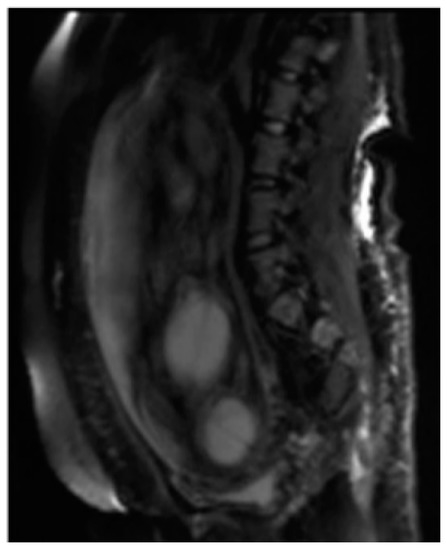

Figure 1.

Fetal magnetic resonance imaging (MRI) of Twin reversed arterial perfusion (TRAP) sequence. Half-Fourier Acquisition Single-Shot Turbo-Spin-Echo (HASTE) T2 Sag. Both the acardiac (signaled by the arrow) and pump twins are visible.